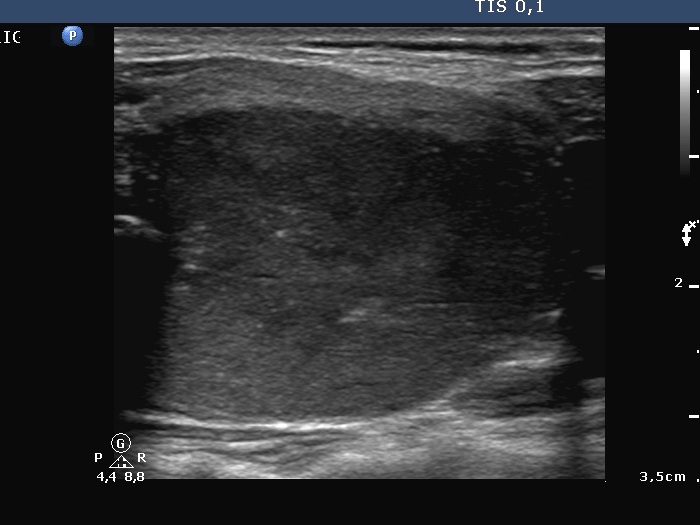

Ultrasonography. The thyroid was diffusely hypoechogenic. The vascularization was increased. The left thyroid was significantly more inhomogeneous than the right lobe. Compare the first two index pictures in the first row with the third and fourth one, right and left lobe, respectively.

1. It seems to be a reasonable assumption that papillary cancer had been already present at the first investigation. It was very unusual that the left thyroid was significantly more inhomogeneous than the right lobe. The former contained relatively large hyperechogenic granules, however, there were no discrete circumscribed lesion in the left lobe.